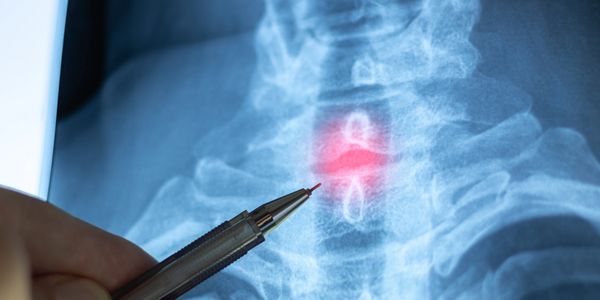

Spinal decompression therapy is a safe, non-surgical treatment designed to relieve pressure on the spine. By gently stretching the spine, this therapy reduces pressure on the discs and nerves, allowing oxygen, water, and nutrients to flow back into the affected areas. This process helps the body heal naturally and can provide lasting pain relief.

During a spinal decompression session, you’ll lie comfortably on a specialized table while gentle traction is applied to the spine. This controlled stretching creates space between the vertebrae, reducing nerve pressure and promoting healing. The treatment is painless, relaxing, and many patients report feeling immediate relief.